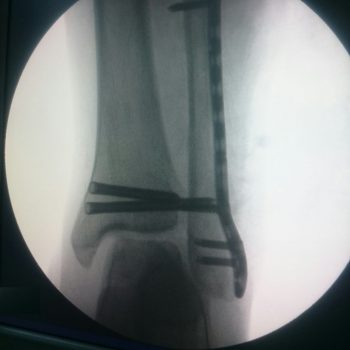

Fibula Locking Plate

Kichik boldir suyagi

Tibia Distal Medial – Qulfli va qulfsiz mixlar

Distal Tibia Medial